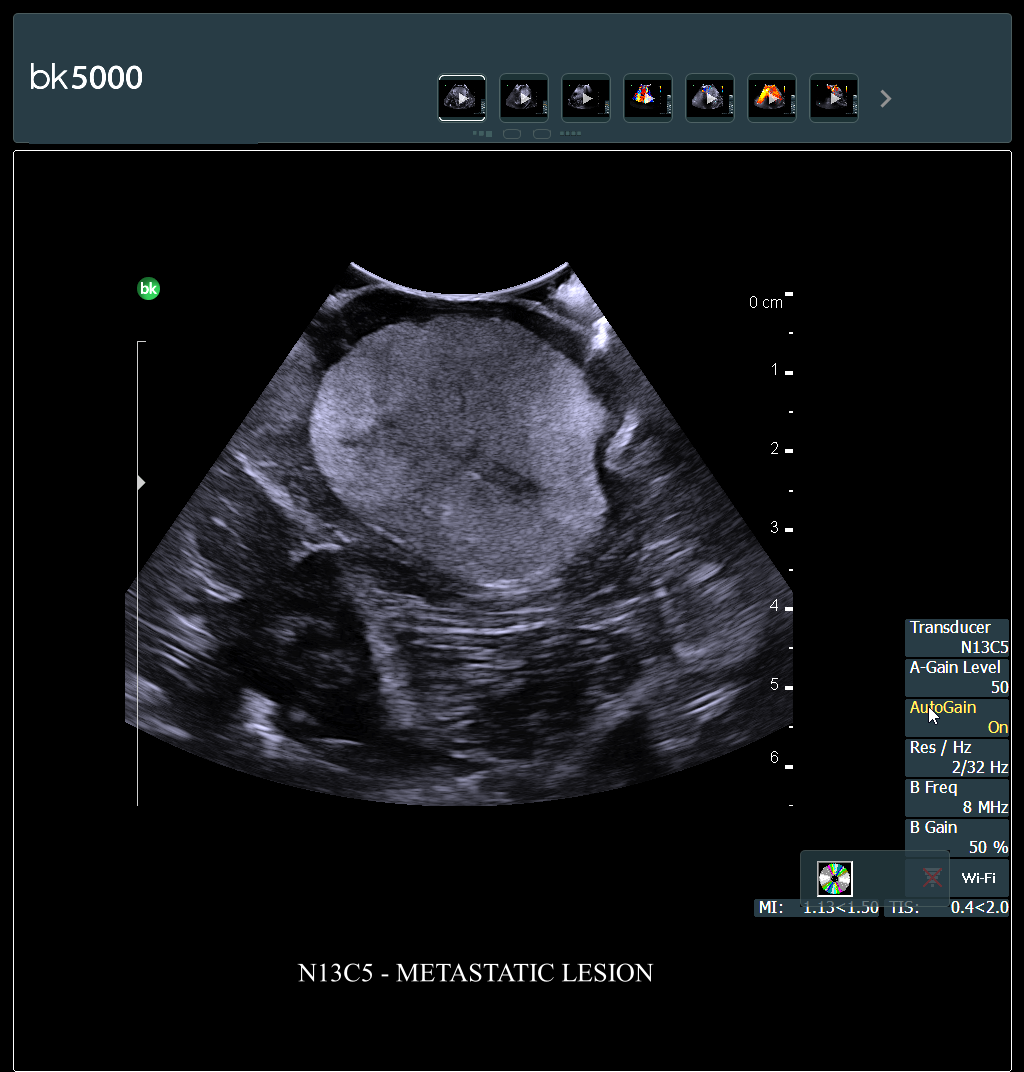

Ultrasound can improve neurosurgical procedures by helping you navigate and identify lesions and anatomical structures in real-time. This is particularly important as the data obtained from a preoperative CT or MRI scan can be outdated at the time of surgery. The bk5000 neurosurgical system provides the highest quality images that allow you to clearly see the margins of a lesion and to determine the best course of action. Using advanced graphics processing technology, this powerful system provides immediate, auto-optimized images that allow you to see the information you need, faster.

The specialized, high-resolution, sterilizable neurosurgery transducers enable you to obtain detailed images of the brain and spinal cord. They have a convenient Smart™ button that lets you activate the transducer, then freeze, store or print the images at the press of a button. Disposable, easy-to-use needle guides assist with targeting lesions.